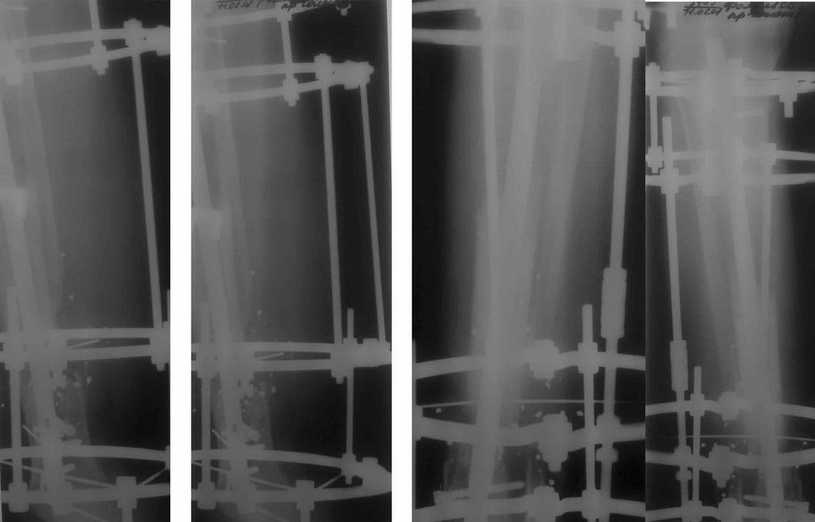

Пример (пациент 46 лет, лечился у нас 4 года назад, внутренний остеосинтез выполнен с определенными погрешностями, но перелом сросся и рецидива инфекции не было): рис. 1,2 - при переводе к нам в институт, рис. 3 - после микрохирругической пластики, рис. 4, 5 - после интрамедуллярного остеосинтеза, рис. 6, 7, 8 - внешний вид и рентгенограммы после окончания лечения

Больному была выполнена операция. после демонтажа аппарата Илизарова столкнулись с "прямо на глазах" сокращением регенерата. Гвоздь сквозь регенерат удалось провести без технических трудностей. Сложности были с репозицией отломков, что связано с выраженным остеопорозом, их короткими размерами. Пришлось применить полер-винт. Выполнили блокирование. По причине укорочения регенерата пришлось повторно смонтировать аппарат Илизарова и начать транспорт фрагмента на гвозде (14 мм). Больному разрешена ходьба с дозированной нагрузкой на больную ногу. Контрольные рентгенограммы прилагаются. Нынешняя ситуация породила ряд вопросов и замечаний: